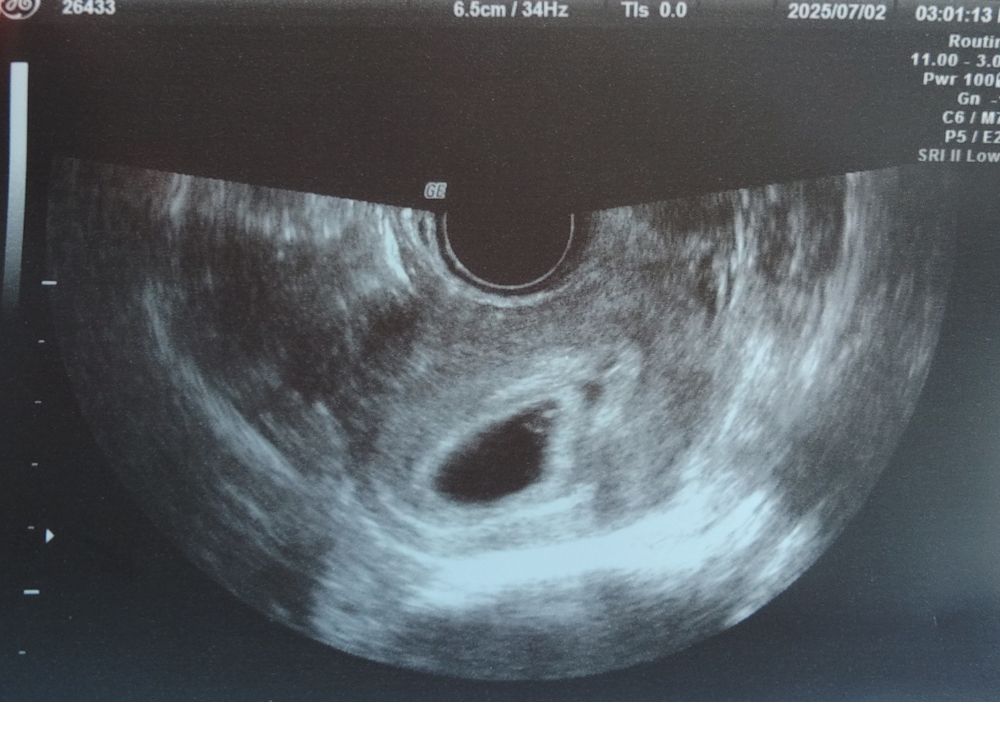

7月に里帰りして、初めて病院に行き、胎嚢・心拍を確認できたときにも安心はできませんでした。